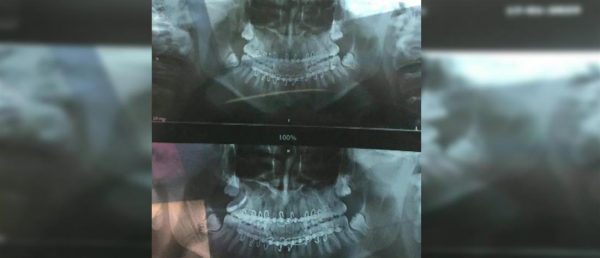

Ο μαθητής είναι 16 χρονών και φοιτά στη Β’ Λυκείου του 2ου ΕΠΑΛ, στο Λουτράκι. Από τον ξυλοδαρμό, υπέστη σοβαρά τραύματα στην κάτω γνάθο και νοσηλεύεται στο ΚΑΤ από τις 16 Ιανουαρίου 2023, οπότε και σημειώθηκε το περιστατικό.

Σοκάρουν οι φωτογραφίες με τα βαριά τραύματα του μαθητή

Οι φωτογραφίες με τα τραύματα του παιδιού, που παρουσιάστηκαν στον ΑΝΤ1, σοκάρουν.

«Το παιδί πονάει, πρέπει να του βάλουν σίδερα στο στόμα για να το ακινητοποιήσουν», ανέφερε σχετικά με την κατάσταση της υγείας του γιου της, η μητέρα.

Προσοχή σκληρές εικόνες: